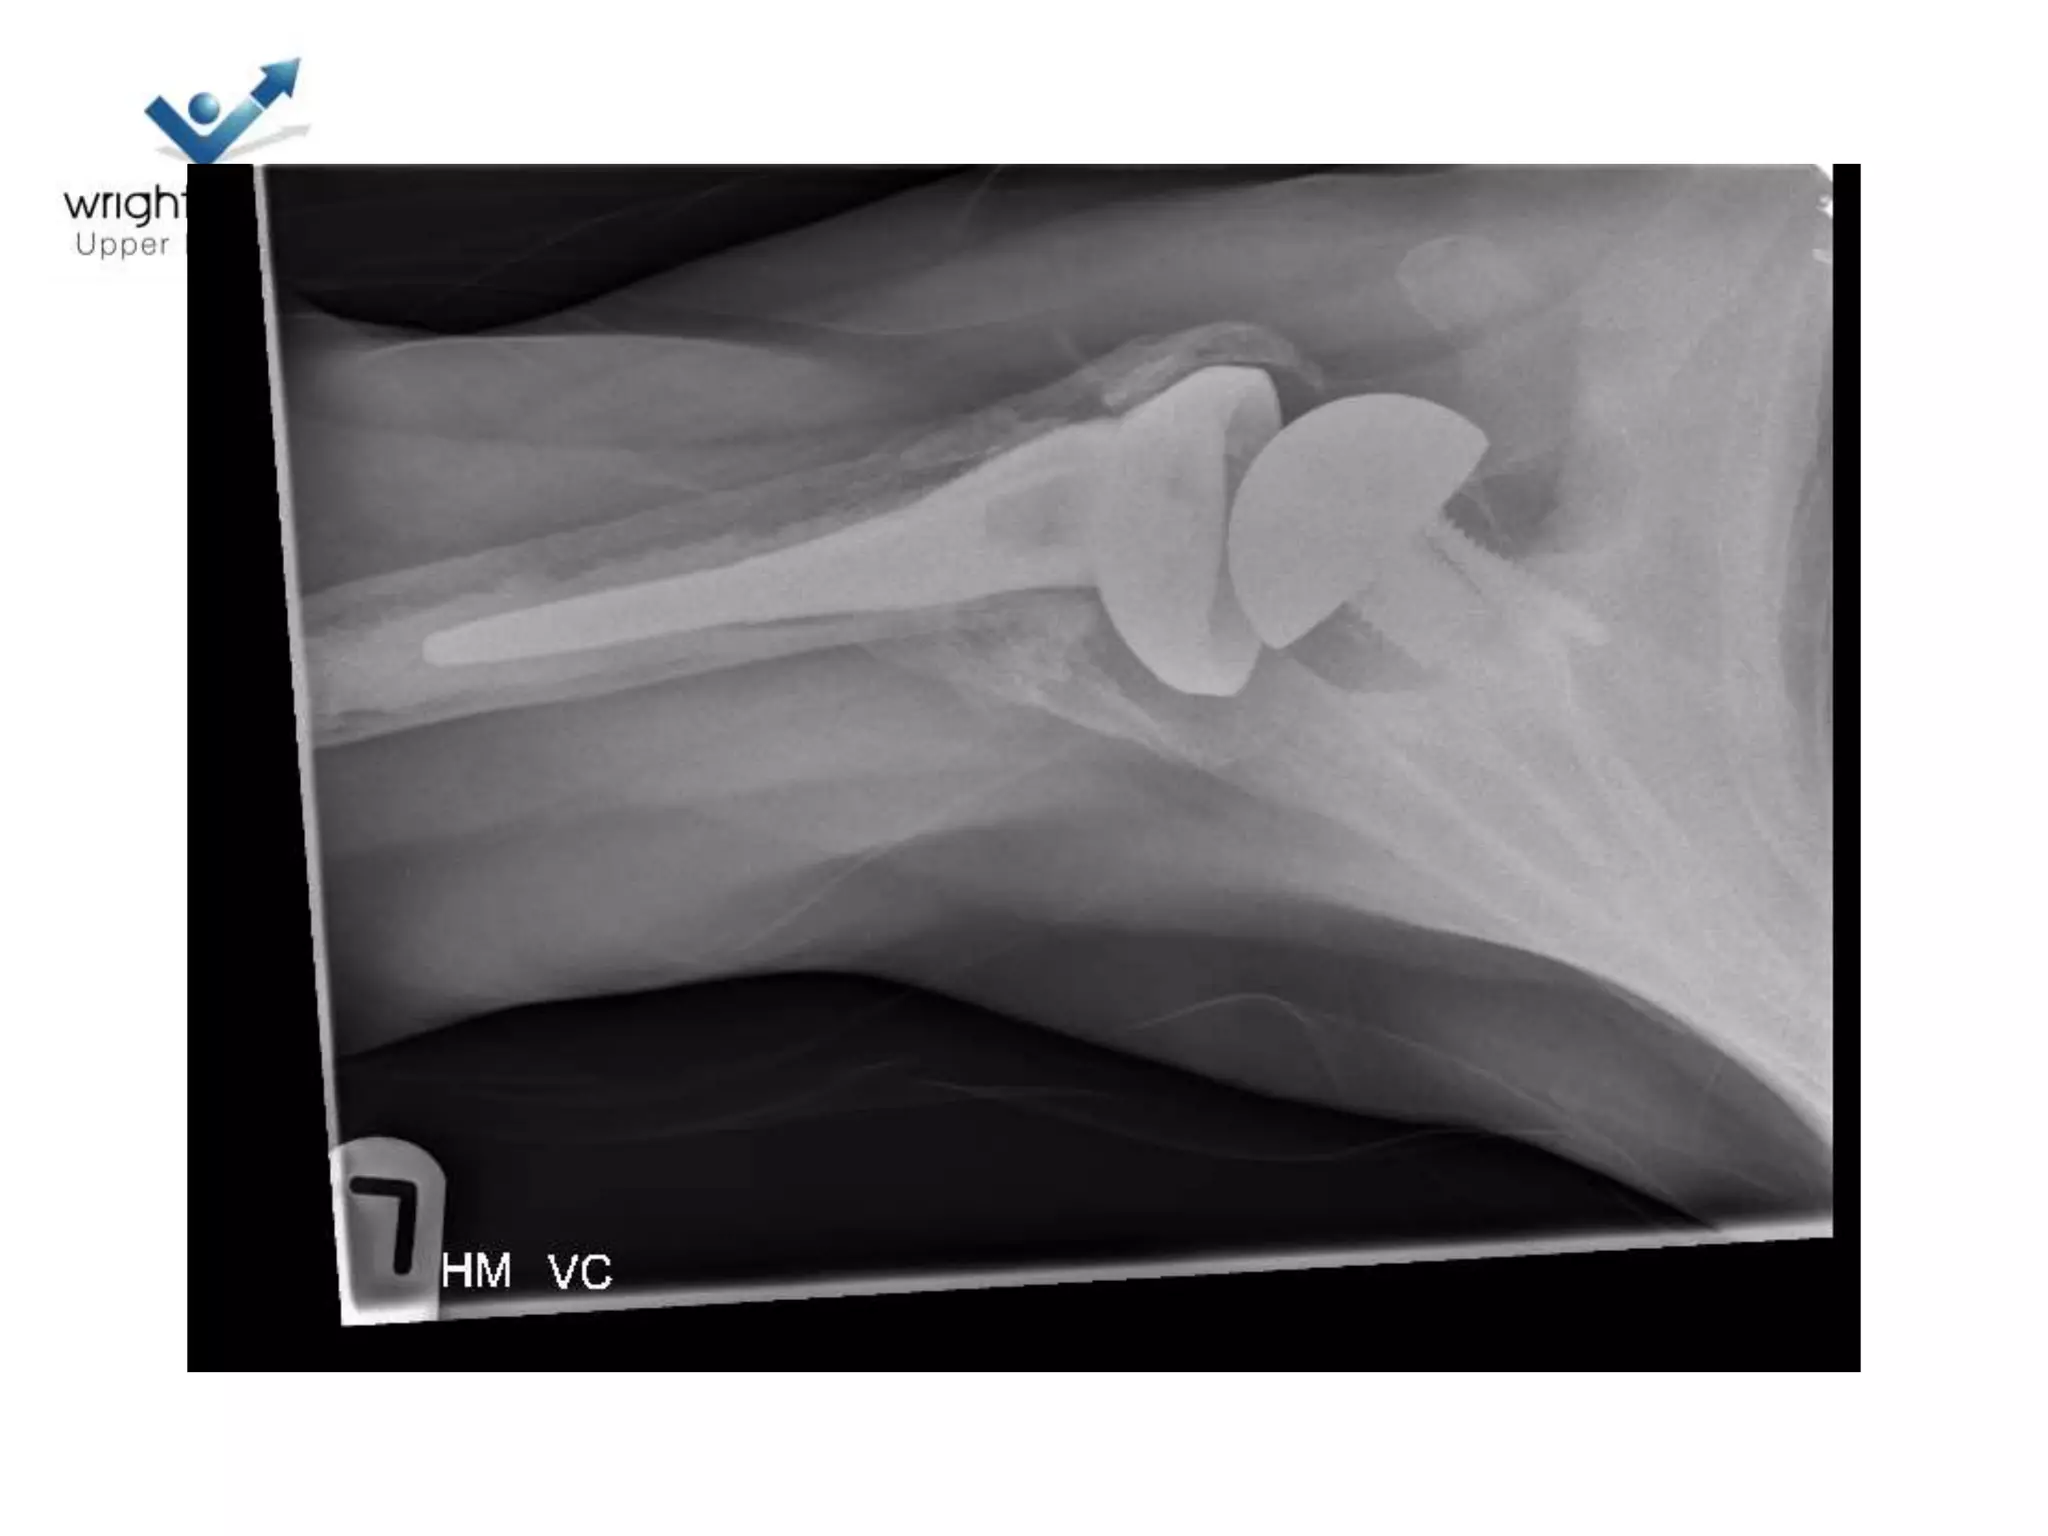

Hemiarthroplasty

• Getting it right

• Depth of prosthesis

• Version of prosthesis

• Size of the head